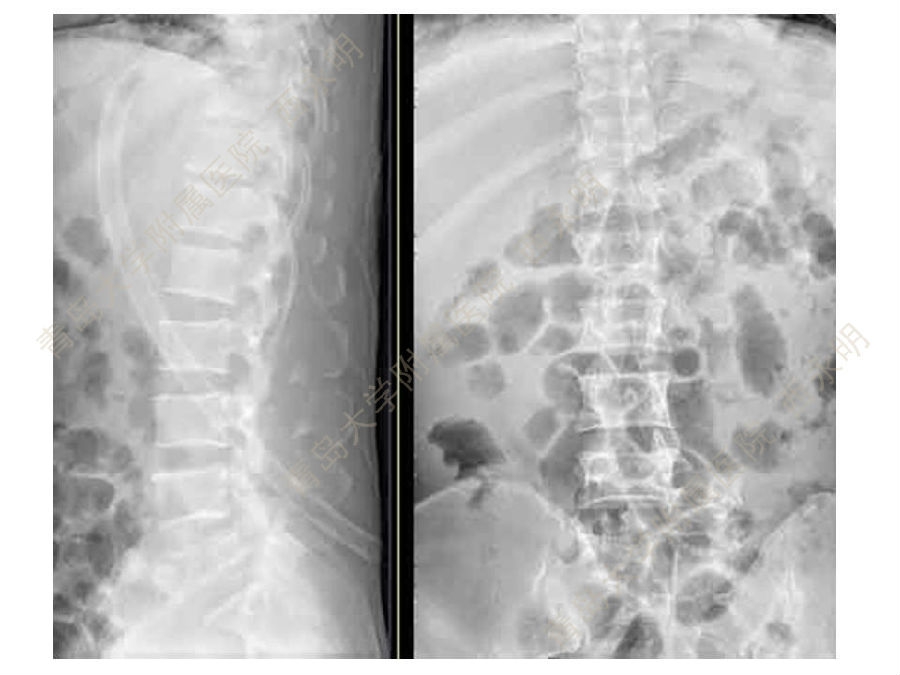

皮质骨螺钉技术及临床应用

颈椎伤病、脊柱畸形和脊柱肿瘤以及颈胸腰椎退变性疾病的微创治疗。长期从事临床一线的医、教、研工作,在多年的临床实践中积累了丰富的经验,并形成了以脊柱外科为专业方向,以颈椎外科、脊柱畸形和脊柱肿瘤为专业特色。